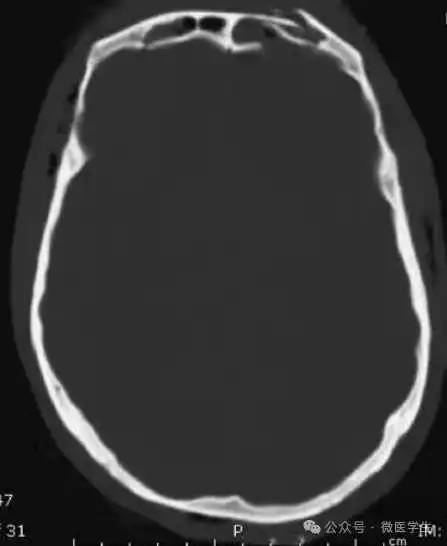

颅脑CT常用的三个窗(图A-C):

- 图A:骨窗(the bone window)

图A:骨窗;主要用于明确骨折、窦腔病变、颅内积气。